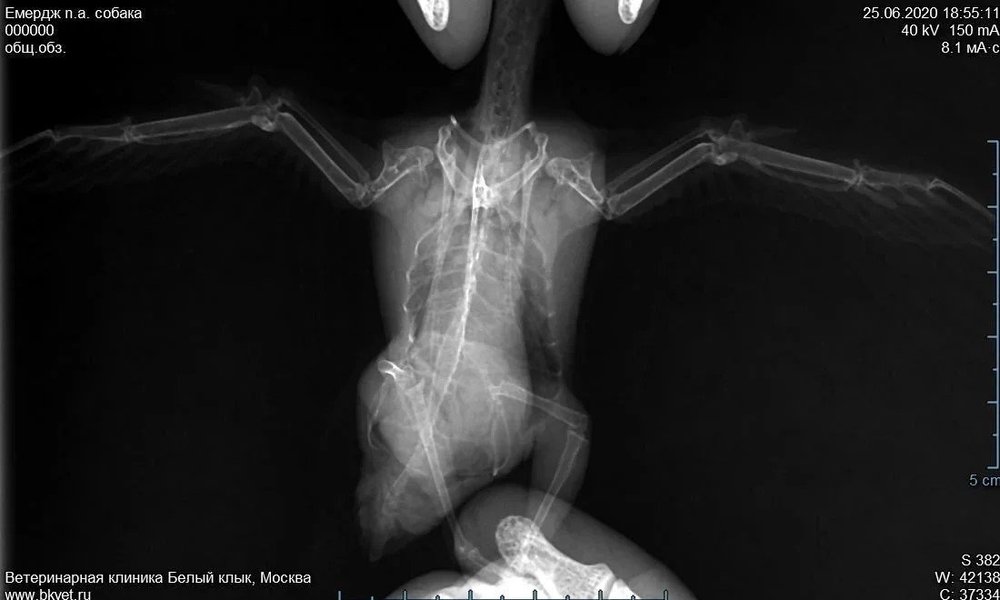

Добрый день! Нашли стрижа 30 мая. На следующий день в клинике у орнитолога сделали рентген. Доктор сказал, переломов нет, скорее всего, ушиб, назначил Мелоксидил.

Спустя  неделю у стрижа был кризис- судороги, выворачивал шейку. Связались с доктором- срочно подкожно физраствор, внутримышечно Тиамин и Байтрил в клювик, дозы рассчитал. К вечеру стриж чувствовал себя хорошо, аппетит вошел к норму. Первый рентген затерялся, сделали другой, на котором, как сказал доктор, стало видно то, чего не было видно на предыдущем рентгене и, как вывод- птица летать не сможет. То ли подвывих, то ли связка- непонятно, как говорит доктор.

Посмотрите, пожалуйста.

Проблема в правым крылом, на рентгене оно слева

На рентгене не вижу ничего криминального. Попрошу совета ещё у коллег